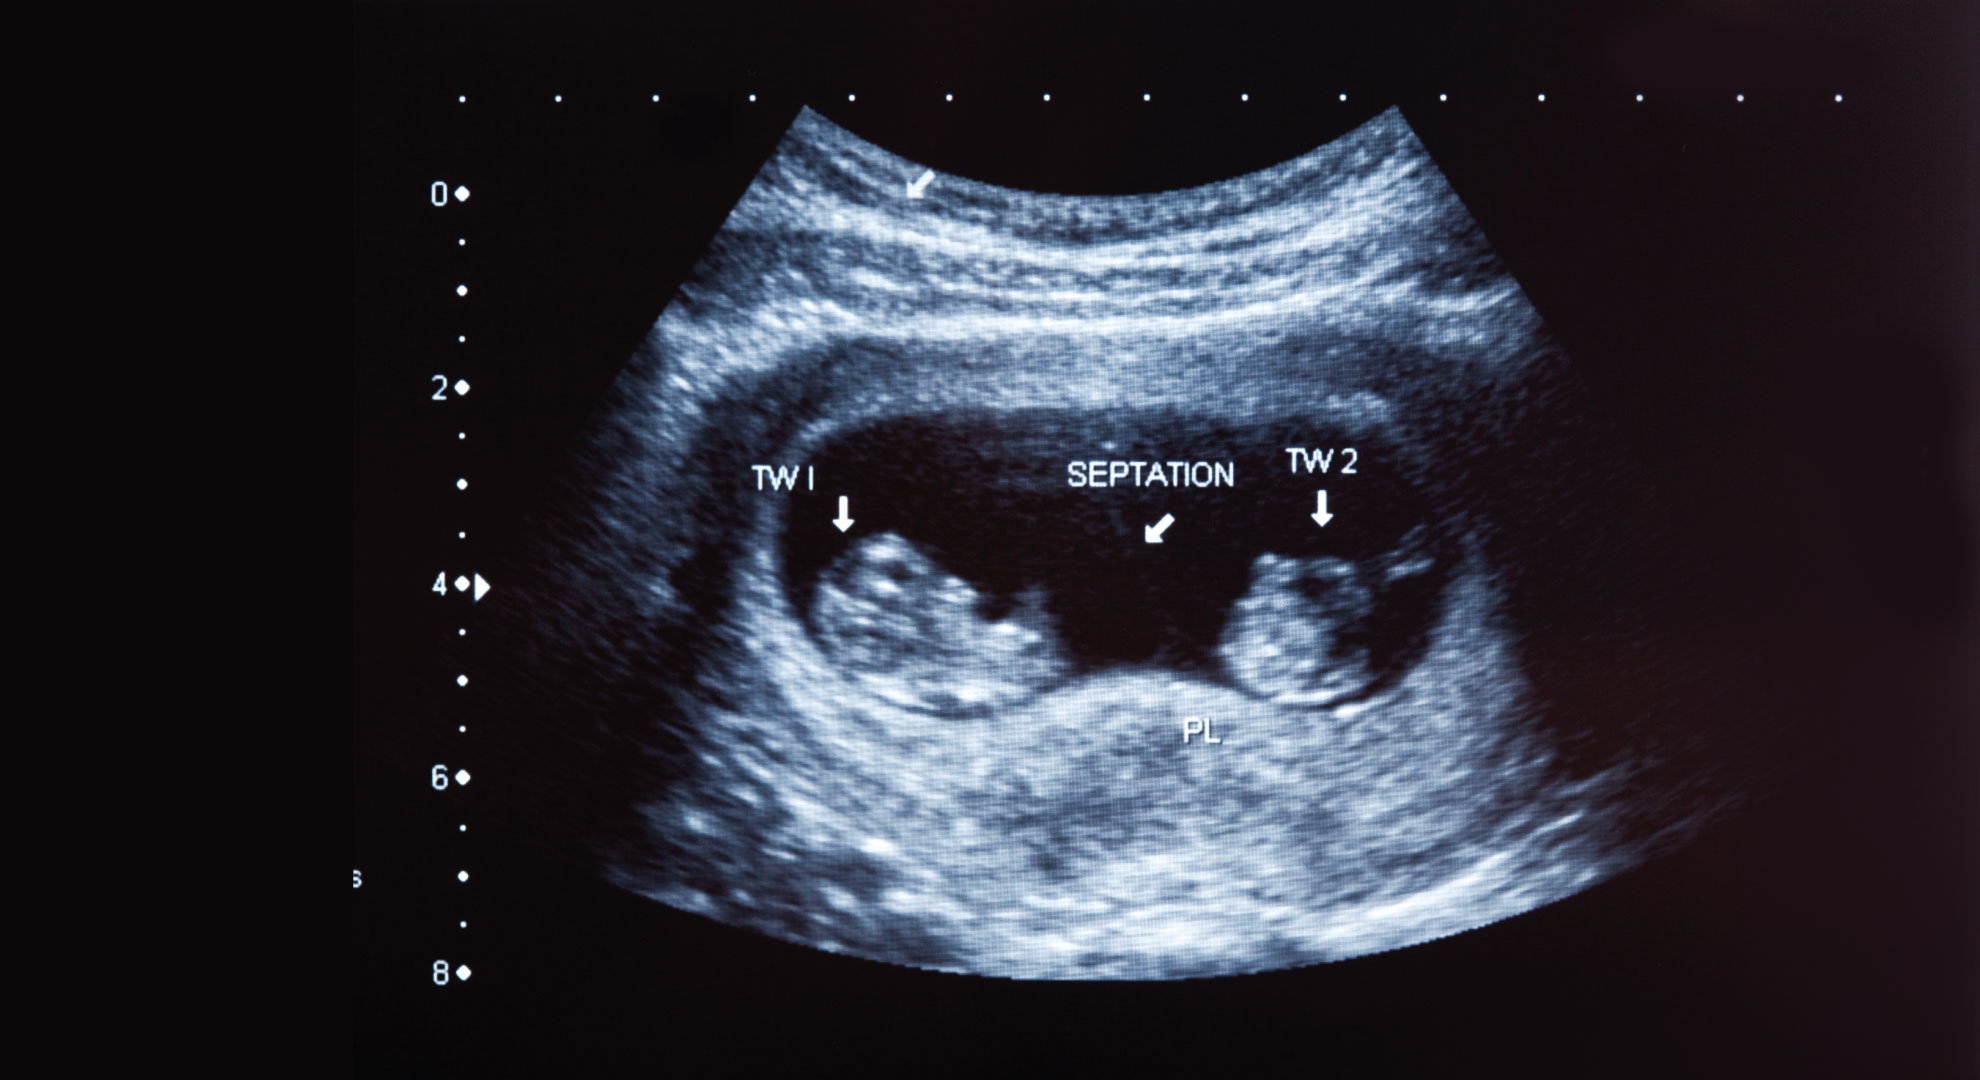

В зависимости от стадии, на которой разделился эмбрион, у однояйцевых близнецов может быть общая плацента и гестационный мешок, а могут быть разные плаценты и отдельные гестационные мешки. В редких случаях однояйцевые близнецы находится в одном амниотическом мешке.